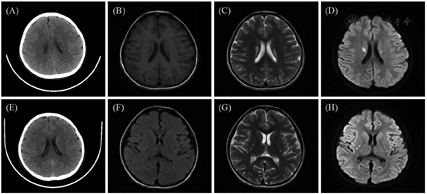

患儿女性,6岁1个月,因"半天内抽搐4次,伴呕吐1次"入院。表现为全身强直阵挛性发作,持续约1 min后自行缓解,间隔数分钟再次发作,共4次,伴高乳酸血症。患儿为第2胎第2产,出生史正常,生后智力、运动发育均落后(17个月会叫妈妈,26个月会走路,4岁会说简单句子)。患儿母亲有糖尿病,父亲体健,非近亲婚配,有1个姐姐,12岁因"酸中毒"死亡。体格检查:身高108 cm(-2 SD),体重15.5 kg(<-2 SD),神志清,双眼外眦上斜,前额低平,前额发际线低,毛发茂盛,分布正常。四肢肌力Ⅴ-,肌张力正常,腱反射可引出,双侧巴宾斯基征阳性,余无明显异常。辅助检查:血乳酸4.8~9.8 mmol/L(参考范围0.5~2.5 mmol/L,下同);心肌型肌酸激酶同工酶167.1 ng/mL(0~3.61 ng/mL);血生化肌酸肌酶282.4~757.6 U/L(25~225 U/L)、天冬氨酸转氨酶162.9 U/L(10~67 U/L)、丙氨酸转氨酶40.7~48 U/L(5~35 U/L)。血糖、血氨、遗传代谢疾病筛查正常。头颅磁共振(MRI)成像:双侧放射冠、豆状核异常信号。定期复查头颅影像学检查发现病灶缓慢进展(图1)。心电图:心室预激。心脏超声:左室肌非对称性增厚伴回声稍增强,左室心内膜局部增厚。

注:(A)~(D)先证者首诊时的影像学检查;(E)~(H)先证者6岁11个月复诊时的影像学检查;(A)计算机断层扫描(CT)显示两侧侧脑室旁卵圆形低密度灶;(B)~(D)磁共振成像(MRI)显示双侧放射冠对称性条带状异常信号,长T1长T2信号,DWI高信号影;(E)CT显示两侧侧脑室旁小片状低密度灶,较前略进展;(F)~(H)MRI显示双侧豆状核、尾状核体部见小斑片状,长T1长T2信号,DWI呈高信号